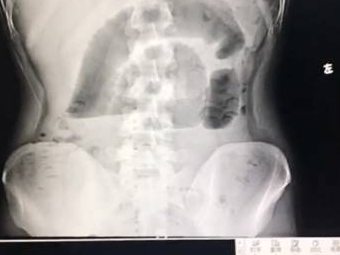

广州一名24岁的小伙子,因为早上太饿,“囫囵吞枣”一口气吃下三个茶叶蛋,基本没有怎么咀嚼,没想到吃下去的茶叶蛋变成了“凶器”,造成了小肠梗阻,不得不住院花一万多块钱做手术取出。网友纷纷评论:这算是史上最贵的茶叶蛋了吧,3个一万。